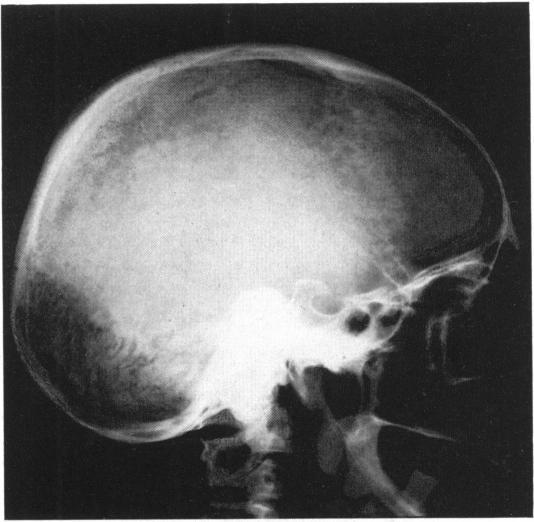

PLATYBASIA WITH INVOLVEMENT OF THE CENTRAL NERVOUS SYSTEM.

Ann Surg. 1942 Aug;116(2):231-50. doi: 10.1097/00000658-194208000-00008.